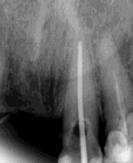

Las Figuras 4-13 son imágenes radiográficas de los dientes de la paciente que presen tan múltiples lesiones periapicales como consecuencia de las necrosis pulpares originadas por la radioterapia. Se realizaron los

tratamientos y retratamientos endodónticos necesarios para preservar los dientes en boca, evitando las exodoncias y por lo tanto minimizando el riesgo de generar osteorradionecrosis.

La Figura 14 muestra la imagen del carcinoma epidermoide de la mucosa yugal antes de la radioterapia. La Figura 15 muestra la radiografía dentoalveolar del incisivo central

Osteorradionecrosis de los maxilares: etiología y prevención

superior izquierdo con diagnóstico de necrosis pulpar y un área radiolúcida periapical extensa.